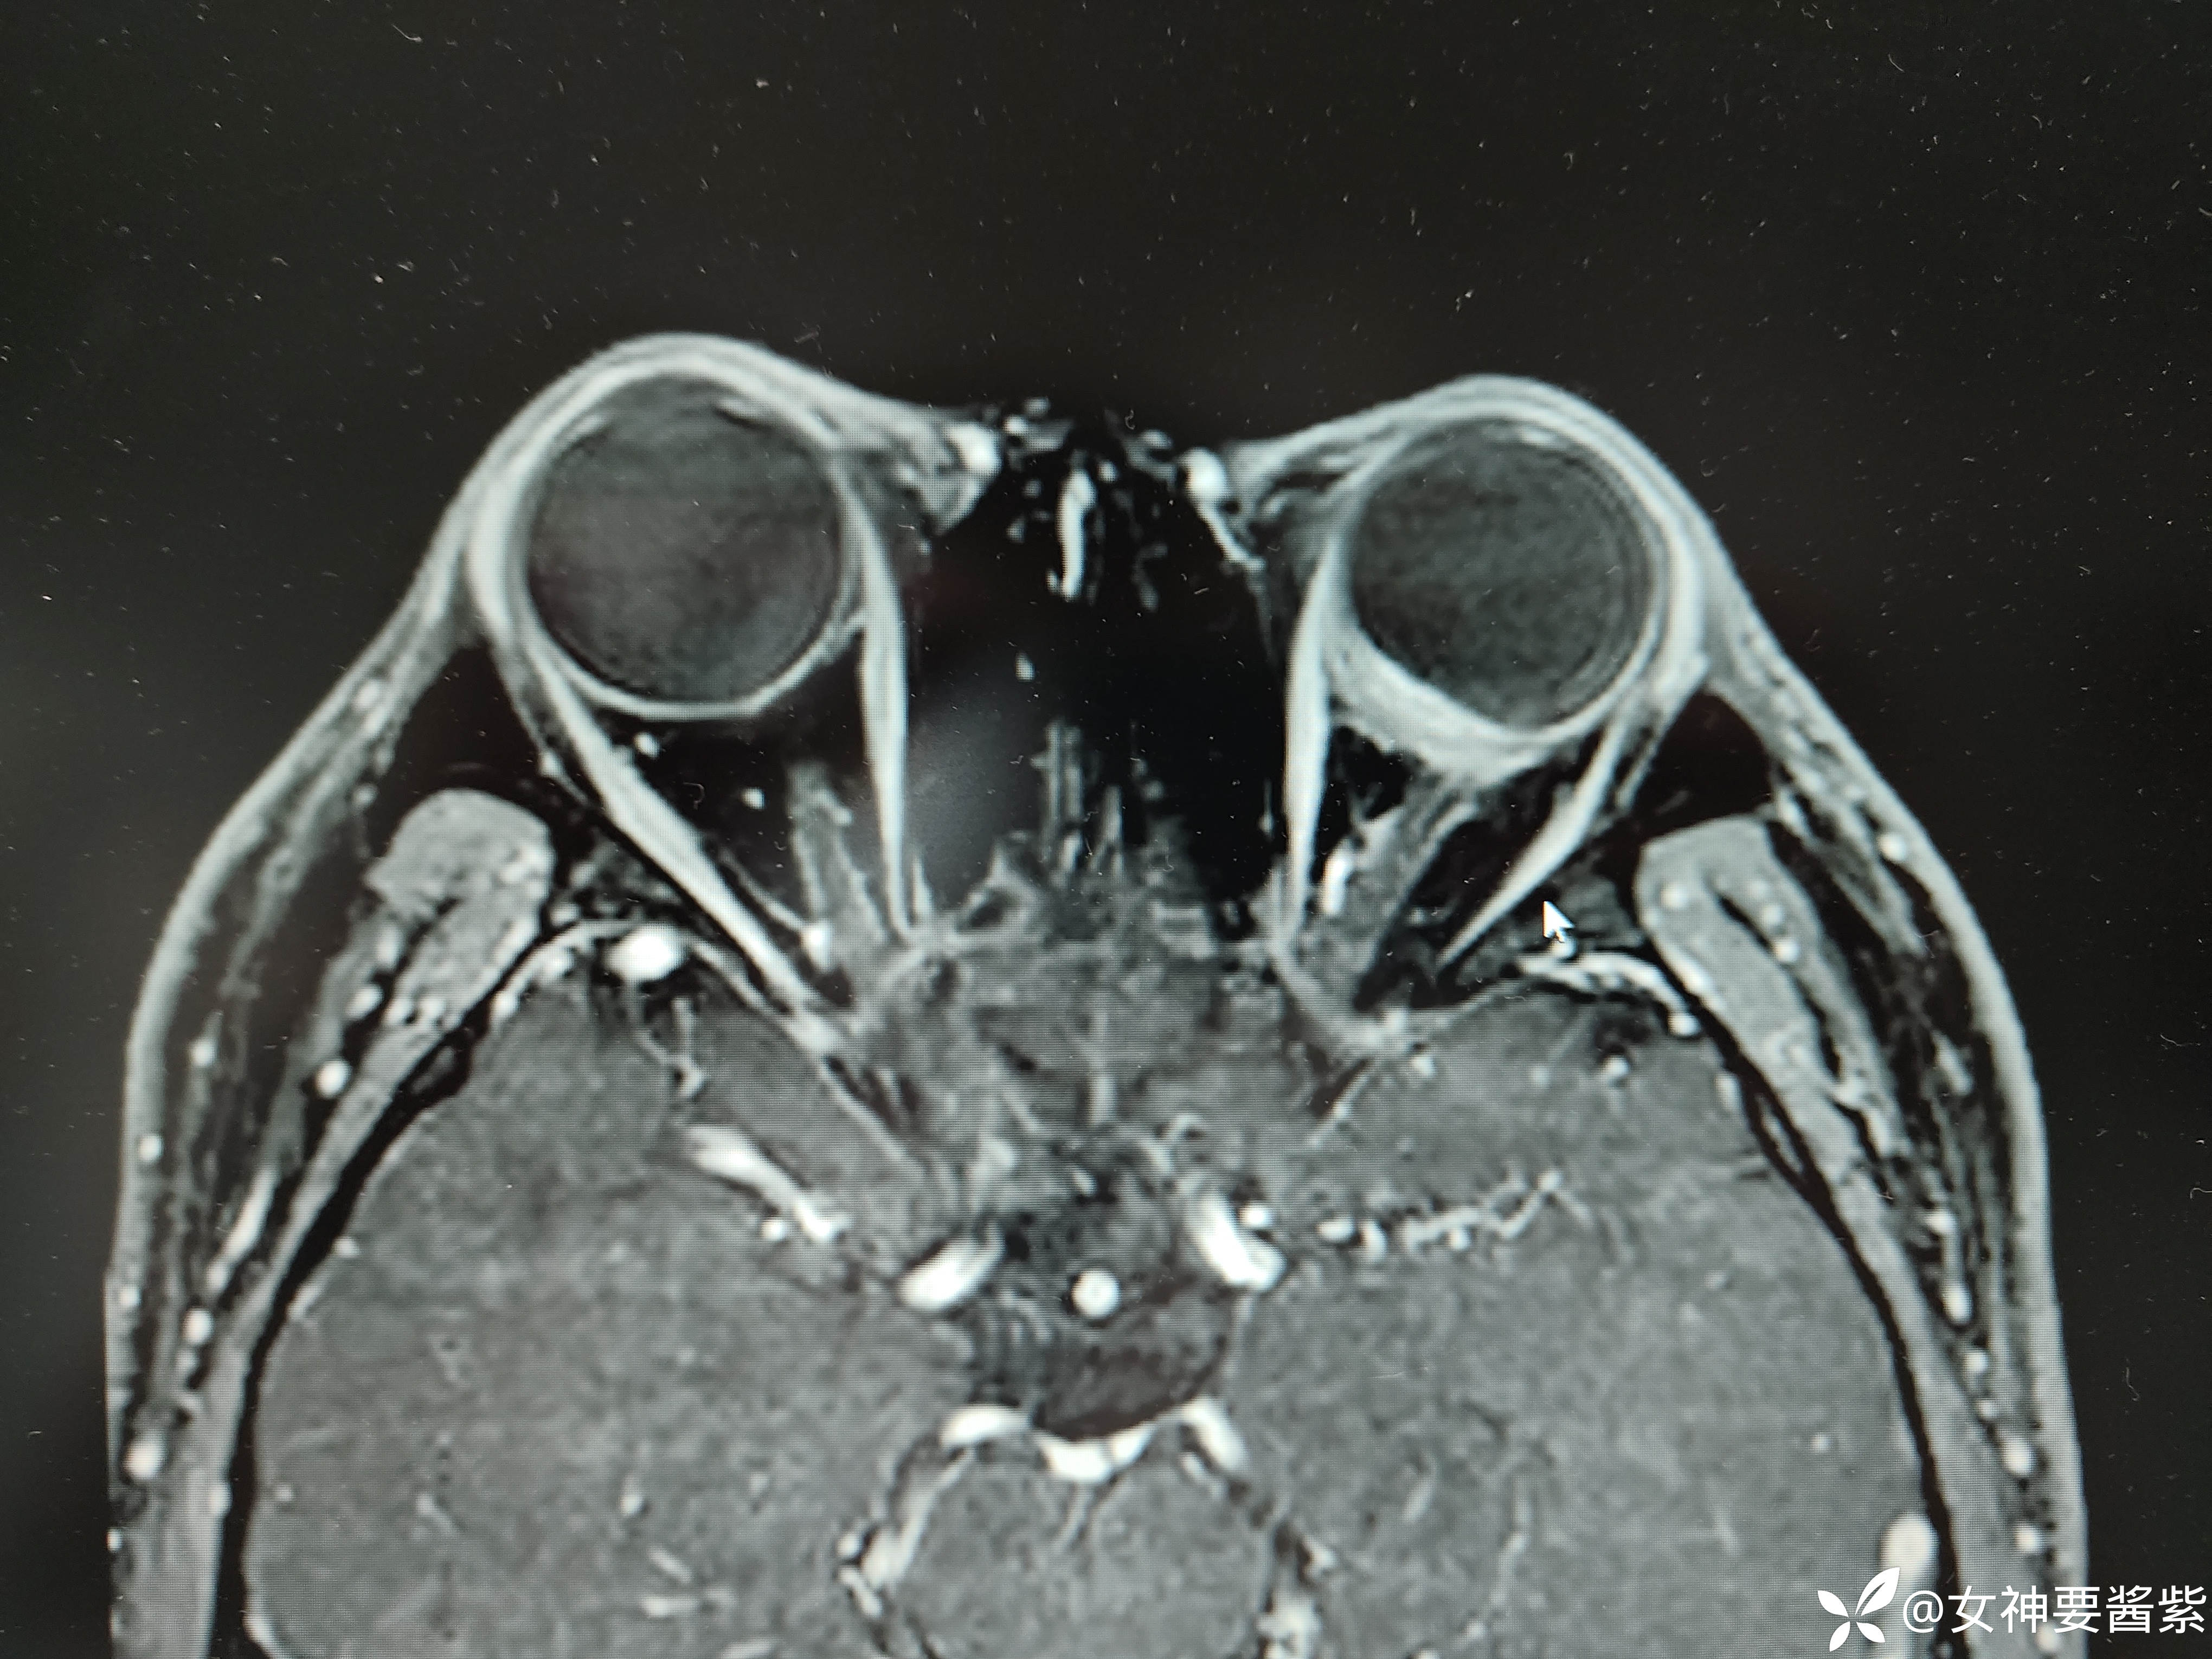

MR